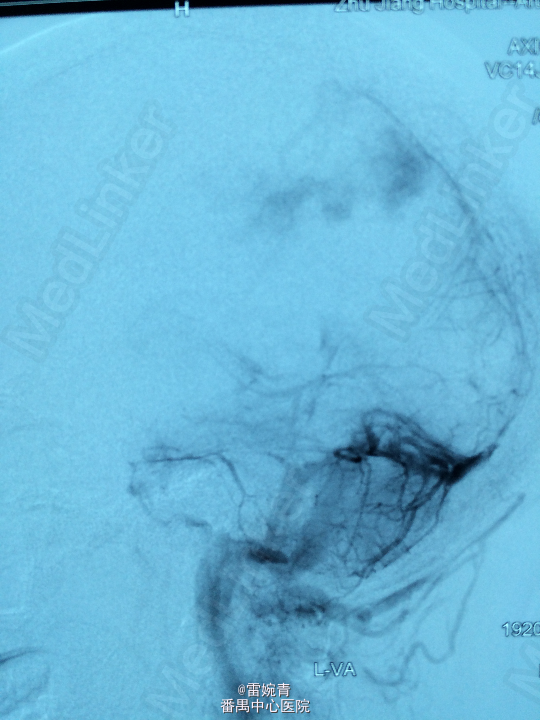

诊断:脑膜瘤 处理:先行DSA检查以明确脑膜瘤的供血动脉情况,见:肿瘤染色,肿瘤主要由左侧眼动脉供血,用Glubran胶将其闭塞,后择期行手术切除治疗。术后病理证实为脑膜瘤。